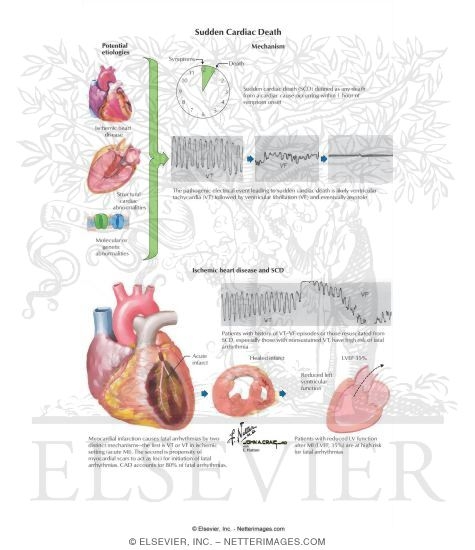

Sudden Cardiac Death

www.netterimages.comSudden Cardiac Death

www.netterimages.comSudden Cardiac Death

Sudden Cardiac Death

www.netterimages.comSudden Cardiac Death

www.netterimages.comSudden Cardiac Death